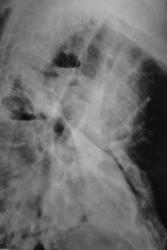

Иллюстрации 3, 4. Справа определяется почти диффузное усиление, обогащение и деформация легочного рисунка, на фоне чего дифференцируются очаговоподобные тени, округлые мелкие просветления. Тень правого корня полностью нивелирована, смещенным вправо средостением.